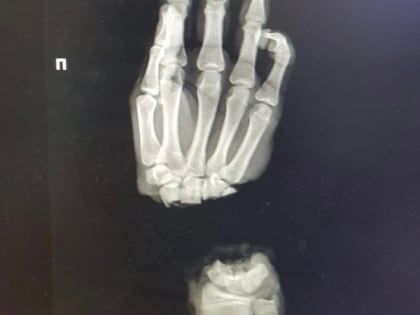

Нижегородские врачи спасли руку 16-летнему подростку

16-летний парень из Владимирской области оказался в нижегородском медучреждении, после того как случайно отрубил себе руку.

Нижегородские медики пришили подростку из Коврова отрубленную руку

Нижегородские медики пришили кисть подростку из Коврова. Юноша поступил в ПИМУ со страшной травмой: он отрубил себе руку, когда колол дрова.

Нижегородские хирурги пришили подростку отрубленную топором кисть

Врачи Университетской клиники ПИМУ пришили подростку отрубленную кисть. Об этом рассказал глава вуза Николай Карякин в соцсетях.

Врачи ПИМУ спасли отрубленную кисть руки 16-летнему подростку

Врачам Университетской клиники ПИМУ в Нижнем Новгороде удалось сохранить отрубленную кисть руки 16-летнему пациенту.